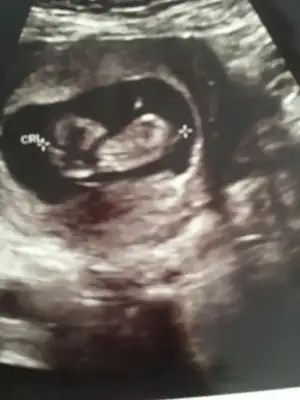

dr soylemeden siz gorun genital nub teorisi ( bebegin cinsiyeti)

• IMG_20190807_164547.webp

IMG_20190807_164547.webp

19,9 KB · Görüntüleme: 75